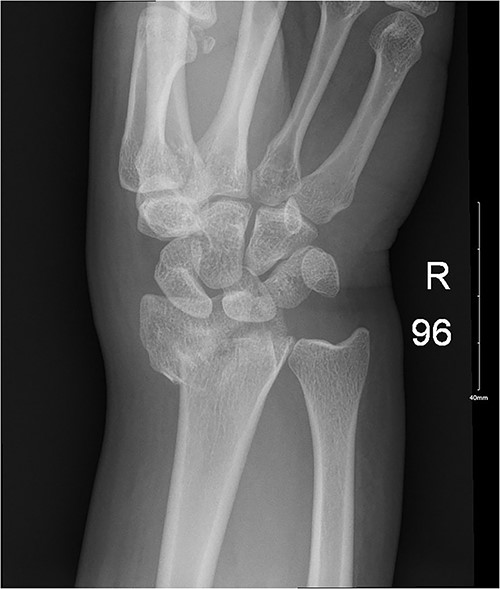

A 29-year-old female presented to the emergency department with pain and deformity of her right wrist as well as a laceration of her right thumb following an MVA with airbag deployment as an unrestrained passenger. The incident happened when another vehicle crashed sideways into the driver’s side while moving at ~50 kmph. There was limited ROM at the MCP joint due to pain. Imaging showed an oblique fracture at the base of first metacarpal bone medially (Fig. 3), so the patient was admitted for wound exploration and repair of other concomitant injuries. The wound was irrigated, the neurovasculature and tendons were observed to be intact, the laceration was sutured, and thumb spica was applied. Subsequent clinic visits showed a hyperpigmented scar as well as a decreased ROM in her wrist and fingers as the radius was still going through the healing process (Fig. 4).

Ongoing healing is seen in the distal radius fracture. The fracture line is barely visible.